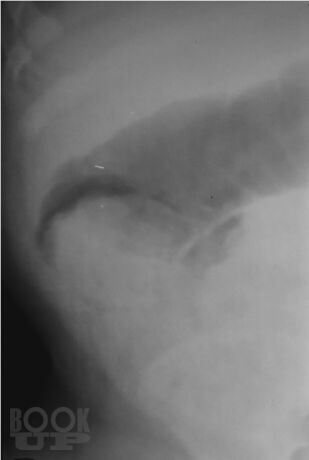

В монографии изложены наиболее актуальные вопросы диагностики и лечения кишечной инвагинации у детей. Представлены данные по истории вопроса, классификация заболевания, диагностический алгоритм. Рассмотрены наиболее частые ошибки в диагностике этого заболевания у детей, подробно обоснован выбор лечебной тактики на основании экспериментального;исследования безопасности консервативного лечения инвагинации кишечника в педиатрической практике. Описаны методики консервативного лечения этого состояния у детей, представлен анализ собственных практических результатов их применения. Отдельно рассмотрены вопросы оперативного лечения инвагинации кишечника у детей, приведено экономическое сопоставление методов лечения этого состояния.